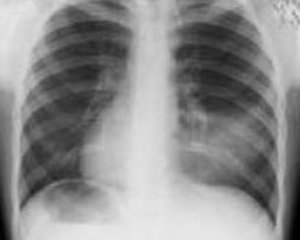

Инструментальные методы диагностики

Основным исследованием, которое позволяет поставить диагноз воспаления легких, является рентгенография. Ее желательно делать на стационарном аппарате, стоя, чтобы врач мог пронаблюдать с его помощью пару вдохов и выдохов до того, как будет сделан снимок.

Если же состояние больного настолько тяжелое, что ему требуется лечение в условиях отделения интенсивной терапии, рентгенография делается с помощью передвижных аппаратов.